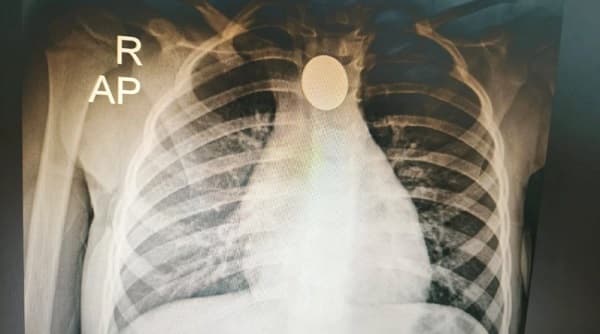

Al llegar al cuartel, los aspirantes al servicio llamaron rápidamente al capitán general Andrés Daniel Gómez López, quien, sin dudar, se dispuso a atender al menor. Tras una evaluación inicial, el capitán notó que el bebé presentaba un tono de piel morado, señal de una posible obstrucción de las vías respiratorias. Con gran destreza, Gómez López aplicó de inmediato la maniobra de Heimlich, en una versión adaptada para el tamaño del pequeño paciente.

Durante esos segundos críticos, el bombero relató cómo intentó inicialmente realizar la maniobra mientras estaba de pie en la puerta. Sin embargo, al ver que el bebé se movía demasiado, optó por sentarse, asegurándose de ejecutar la técnica de manera precisa. La maniobra resultó efectiva, logrando que el bebé expulsara la obstrucción y pudiera volver a respirar.

Luego de la maniobra, el pequeño fue puesto en observación y se le suministró oxígeno durante tres minutos para estabilizar su respiración. Con el niño fuera de peligro, la madre, visiblemente aliviada, expresó su profunda gratitud hacia el equipo de bomberos, destacando la rapidez y precisión de sus acciones.